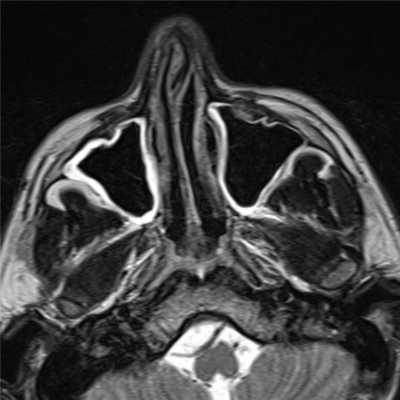

Слева — КТ-снимок одонтогенной кисты в верхнечелюстном синусе, справа — МР-фото образования (указано стрелкой) в гайморовой пазухе

Компьютерная и магнитно-резонансная томография отличаются по своей сути. КТ подразумевает воздействие на организм рентгеном. Изображение формируется в результате улавливания аппаратом Х-лучей, прошедших сквозь рассматриваемую анатомическую область. Плотные структуры организма в большей степени поглощают излучение, поэтому на снимках выглядят светлыми. КТ незаменима для исследования костей. Мягкие ткани лучше отображаются после введения контраста на основе йода. Компьютерная томография занимает несколько минут, поэтому востребована в экстренной медицине.

Магнитно-резонансное изображение измененной лобной пазухи

В основе МРТ лежит воздействие на организм магнитного поля, под влиянием которого меняется траектория движения протонов водорода. Томограф улавливает импульсы и преобразует их в картинку.

Водород есть в тканях, насыщенных жидкостью, поэтому МРТ детально показывает рыхлые структуры организма. Оборудование мощностью от 1,5 Тл дает подробные снимки изучаемой области. Изображения производят послойно, с шагом от 1-2 мм. Это позволяет выявлять патологические очаги размером от 3 мм.

МРТ пазух носа показывает мягкотканные элементы синусов. По характерным морфологическим изменениям, искажению сигнала, особенностям распределения контраста можно сделать выводы о наличии, распространенности и сути патологического процесса.

Магнитно-резонансная томография дает возможность изучить кровеносные сосуды без применения контраста. КТ и МРТ дополняют друг друга и применяются в различных ситуациях. Сочетание методов позволяет получить максимум сведений о патологических изменениях в носовых раковинах, костных тканях и рыхлых структурах синусов.